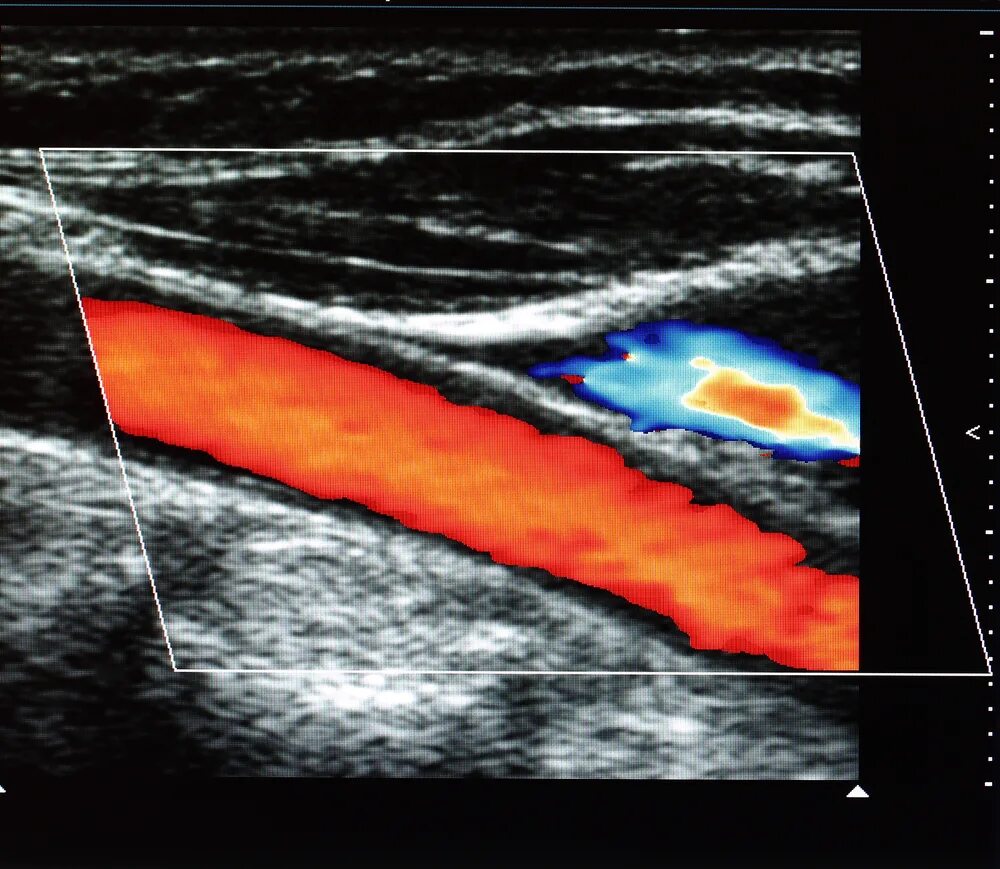

Атеросклероз на узи